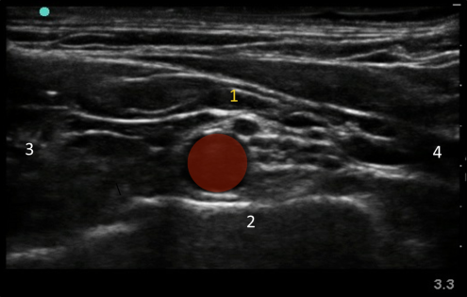

Interscalene Nerve Block - Lower Neck Ultrasound Anatomy Image

1. Brachial plexus

2. 1st Rib

3. Medial

4. Lateral